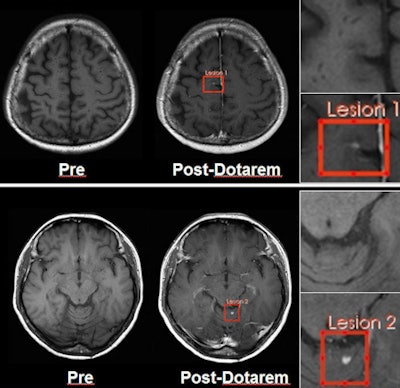

Images show two lesions in a 41-year-old woman with hemangioblastoma disease, acquired on 3-tesla MRI. Images at left are precontrast; images at right are after Dotarem administration. Image courtesy of Guerbet.Experience with NSF indicates that the agents are likely to be safest if they have either macrocyclic or ionic properties, and Dotarem has both, Carrara said. Regarding the agent's safety profile, there have been 37 million administrations of Dotarem since it came on the European market in 1989, and there has been no confirmed case of NSF that could be attributed to Dotarem when used exclusively without any other GBCA in a patient.